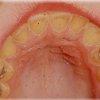

Ülemise hambakaare kitsenemine ehk tagumiste hammaste risthambumus

Hammustades on näha, et alumine hambakaar on laiem kui ülemine. Tagumine risthambumus võib olla kas mõlemapoolne või ühepoolne ja sageli hambakaarte keskjooned hammustades ei ühti. Tagumist risthambumust võib esineda 10...